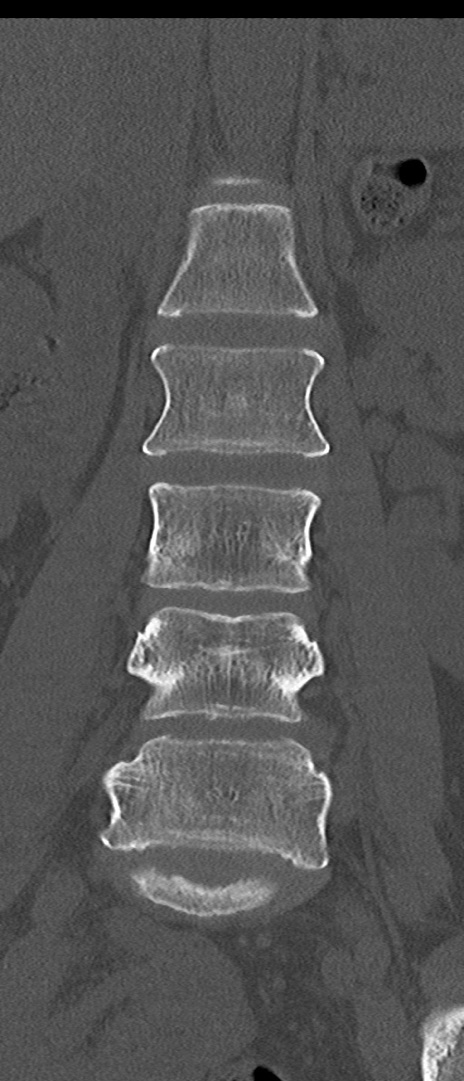

腰椎CT

横断像